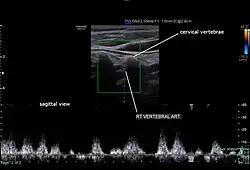

Typically, blood flow velocities in the carotid artery are measured in terms of peak systolic velocity (PSV) and end diastolic velocity (EDV).[15]

Normally, vertebral artery blood flow velocity can be 63.6 ± 17.5 cm/s during PSV and 16.1 ± 5.1 cm/s during EDV according to a study done by Kuhl et al.[16] Due to vertebral artery dominance, measurements can vary on both sides, for example, another study by Seidel et al. found that the right side had an average of 45.9 cm/s and the left side 51.5 cm/s during PSV, and 13.8 cm/s on the right side and 16.1 cm/s on the left side during EDV.[15][17]